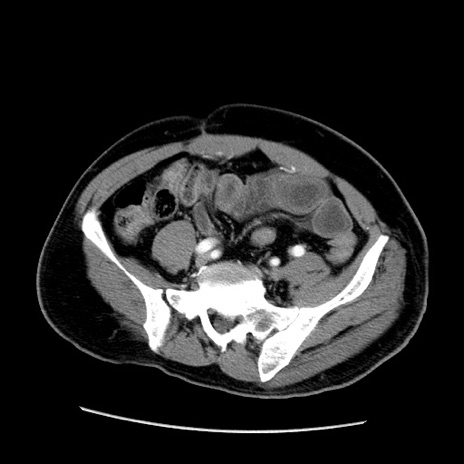

冠状断像

【症例】50歳代男性

【主訴】腹痛

【現病歴】AVMからの被殻出血のため回復期リハ病棟入院中。 本日午後3時頃急に下腹部痛が出現した。

【既往歴】AVM、被殻出血、虫垂炎、高血圧

【身体所見】意識晴明、左半身不全麻痺、会話の理解は良好、36.5°C、腹部:膨隆、全体に板状硬、下腹部正中に圧痛点あり、反跳痛-、筋性防御不明、右下腹部にope scar

【データ】WBC 9400、CRP 0.06